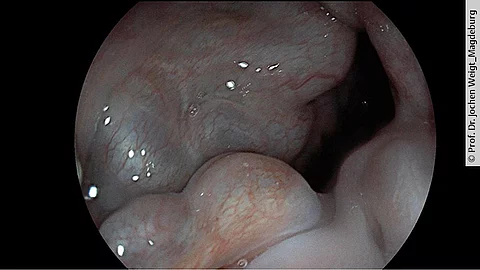

Darmkrebs ist in Deutschland häufig – aber durch Vorsorge vermeidbar. Die Deutsche Gesellschaft für Gastroenterologie, Verdauungs- und Stoffwechselkrankheiten (DGVS) erklärt, wie Stuhltest und Koloskopie Leben retten können und welche Methode sich wann eignet.